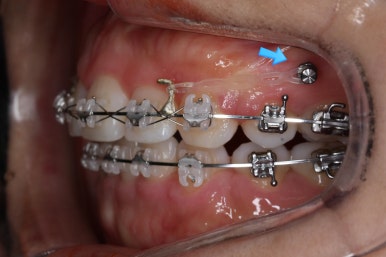

입안 모습입니다.

윗니와 아랫니 모두 각각 보면 가지런해 보이며 발치를 했던 자리도 거의 다 메워져서 양호해 보입니다. 훑어 보면 굳이 더 교정을 해야할 부분이 있을까? 싶겠지만 다음 사진을 보면 알 수 있습니다.

입 속 좌우 모습인데요. 문제점은 다음과 같이 있었어요.

윗니와 아랫니의 교합이 톱니바퀴처럼 맞물리지 않고 1대1 정면으로 맞닿고 있었습니다.

앞니쪽도 보면 윗니와 아랫니의 앞뒤 간격이 크게 차이나는 것을 볼 수 있습니다.

발치교정을 하였을 때, 흔히 나타나는 문제인데 앞니의 각도가 안으로 매우 굽어져 있습니다. 옥니라고 하며 발치를 한 공간을 너무 당겨 넣다보면 발생할 수 있습니다.